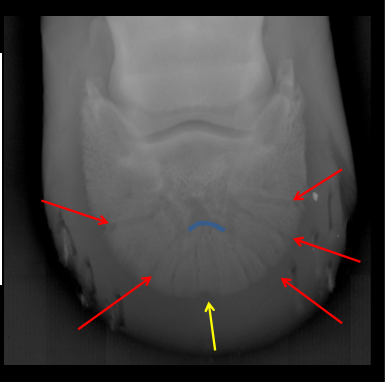

the palmar process

what does number one represent?

the palmar notch

number 3 is..

the sole border

the border at number 2 is called...

crena

the sole border (2) includes a notch that is called the ...

the palmar grooves

what do the lines represent?

extensor process

1 is the...

palmar processes

2 are the...

palmar notches

3 are the...